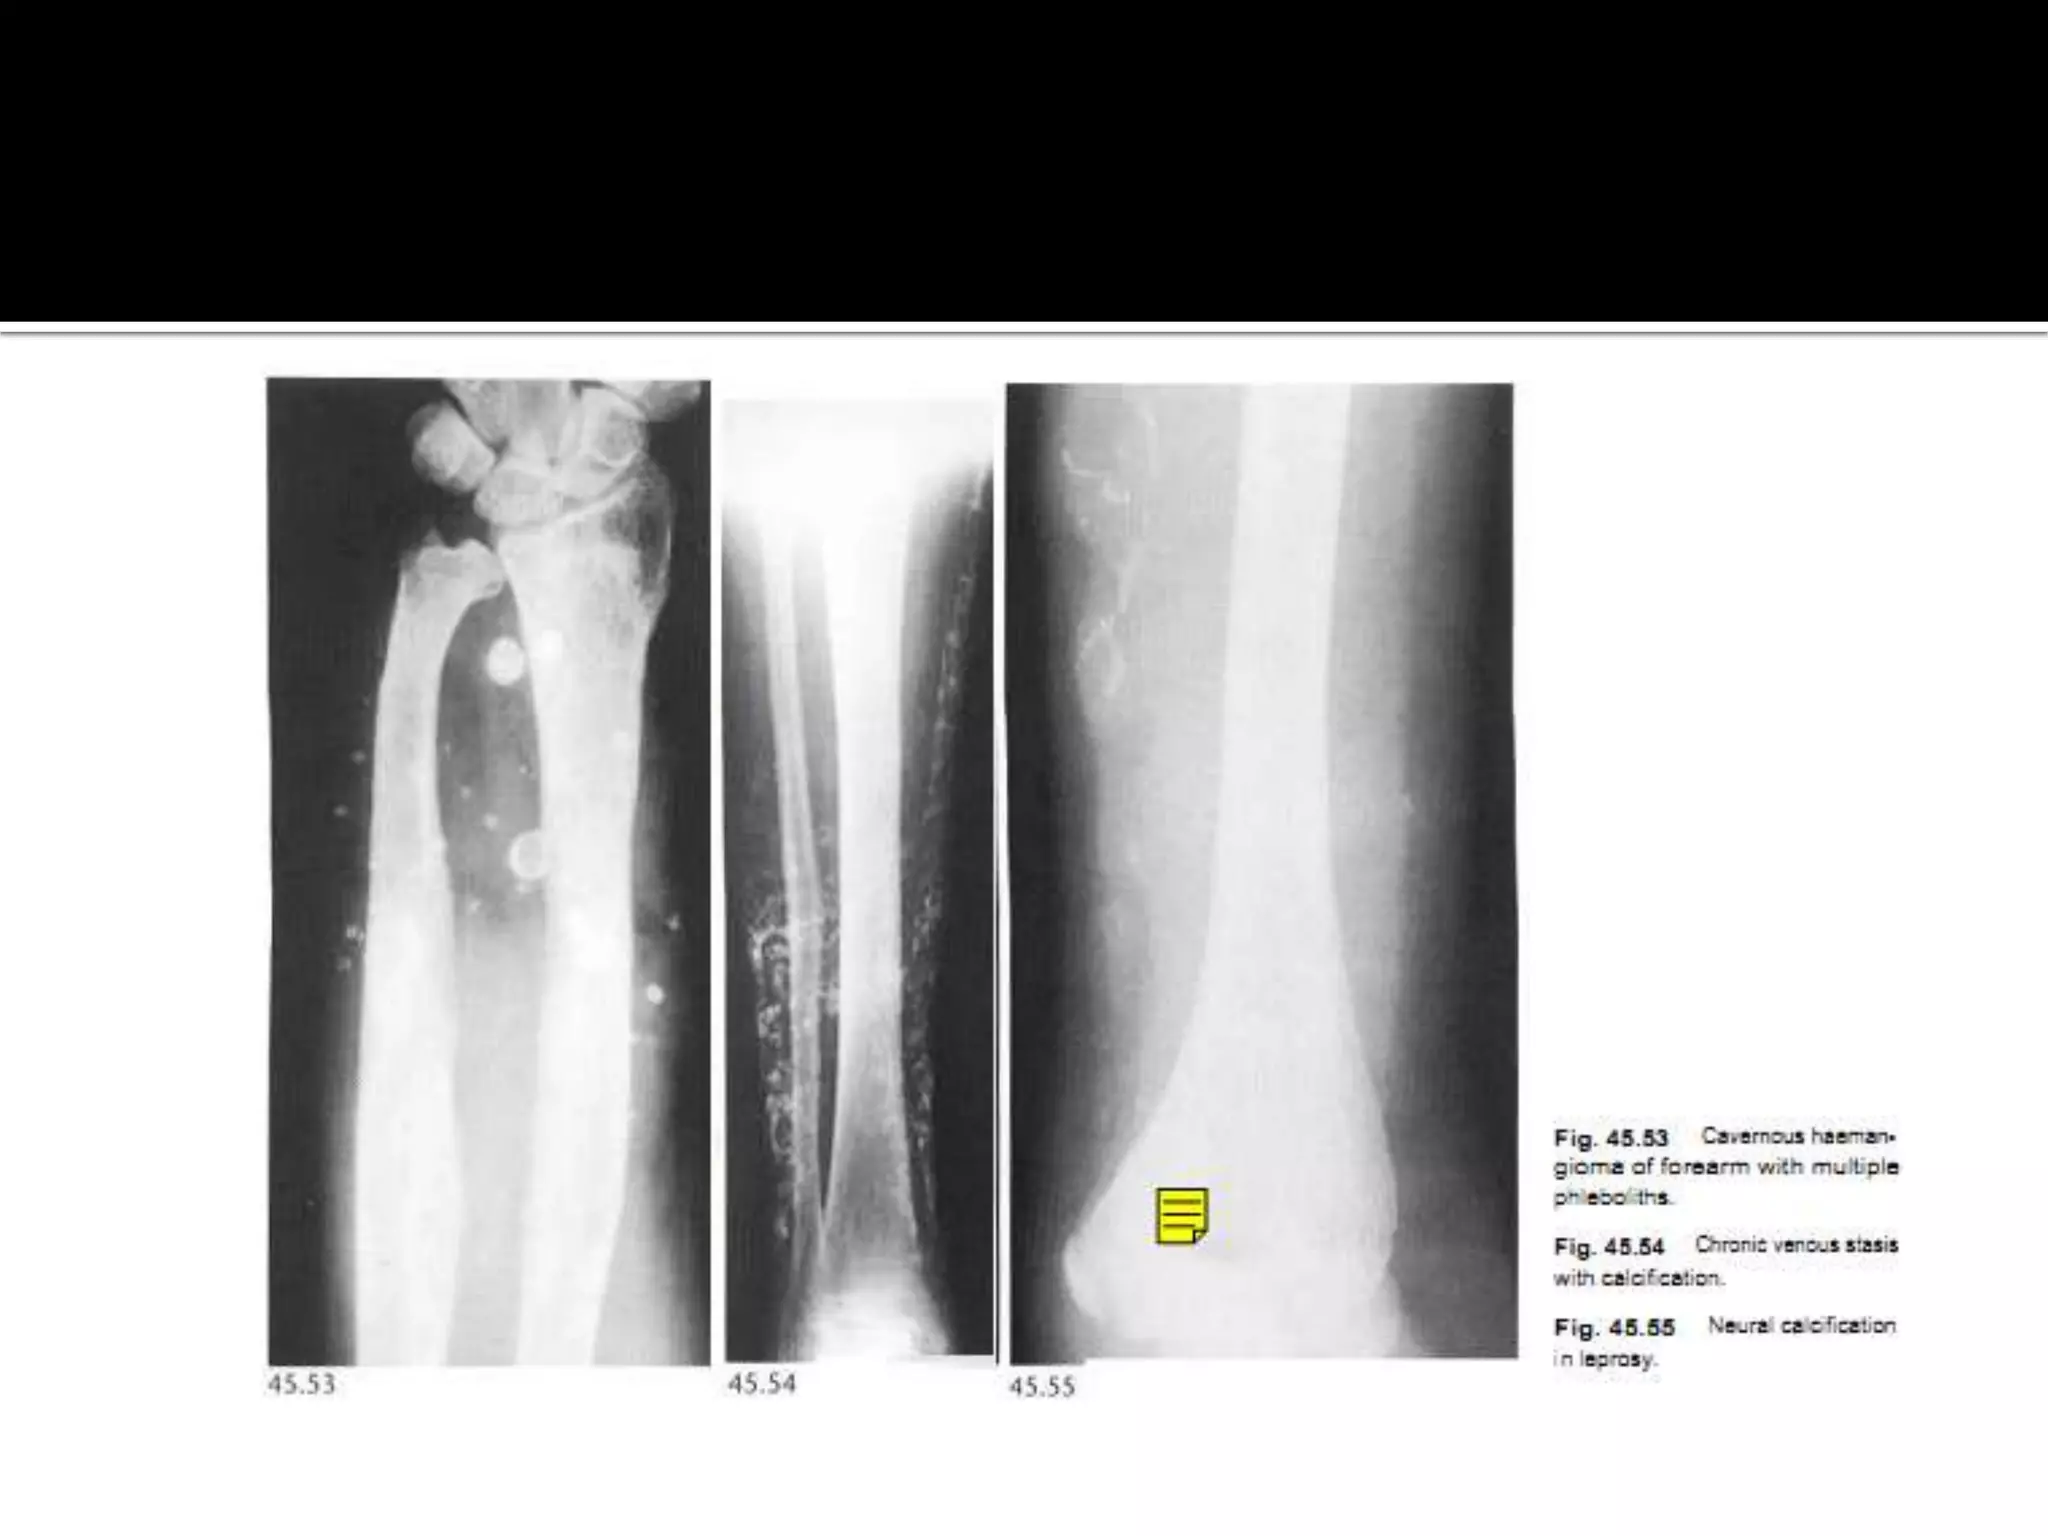

Calcification in veins

 Phlebolith is a calcified thrombus in a vein ( 3-5 in

length and has a central lucency)

 Normal finding in uterine and prostatic veins in the

pelvis

 when a focal collection of phleboliths is seen

elsewhere is a characteristic

cavernous haemangioma.

 Chronic venous stasis may cause subcutaneous

calcification in a linear branching or plaque like

pattern.

 Ulceration, phleboliths and well- organized

periosteal reactions my also be present.

 Sometimes thrombus in a vein may calcify along its

length.

 Neural calcification. Rare but may occur in

Leprosy & neurofibromatosis.

Small vessels calcificationDM,Hyperparthyroidism.  Calcification of the vessels is not a feature of Buerger,s disease. Calcification in veins  Phlebolith is a calcified thrombus in a vein ( 3-5 in length and has a central lucency)  Normal finding in uterine and prostatic veins in the pelvis  when a focal collection of phleboliths is seen elsewhere is a characteristic

• 8.

cavernous haemangioma.  Chronicvenous stasis may cause subcutaneous calcification in a linear branching or plaque like pattern.  Ulceration, phleboliths and well- organized periosteal reactions my also be present.  Sometimes thrombus in a vein may calcify along its length.

• 9.

 Neural calcification.Rare but may occur in Leprosy & neurofibromatosis.